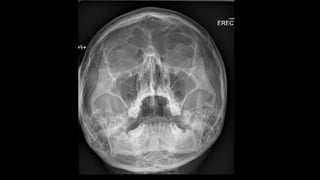

 The projection is performed with the patient seated facing the

receptor.

 The patient’s nose and chin should touch the receptor midline, and

head is tilted so that the orbitomeatal line is 45 to the receptor.

⁰

 The horizontal central line should be at the level of lower orbital

margins.

 The beam centred on the receptor should coincide with the patients

anterior nasal spine.

• collimation

• superior to the skin margins

• inferior to include the most inferior aspects of the skull

• lateral to include the skin margin

Occipitomental view

Maxillary and frontal sinusitis

Gas-fluid levels (red arrows), indicating acute sinusitis. Mucosal thickening of

the maxillary sinuses (blue arrows), suggestive of chronic sinusitis.

z  The projectionis performed with the patient seated facing the receptor.  The patient’s nose and chin should touch the receptor midline, and head is tilted so that the orbitomeatal line is 45 to the receptor. ⁰  The horizontal central line should be at the level of lower orbital margins.  The beam centred on the receptor should coincide with the patients anterior nasal spine. • collimation • superior to the skin margins • inferior to include the most inferior aspects of the skull • lateral to include the skin margin Occipitomental view

Maxillary and frontalsinusitis Gas-fluid levels (red arrows), indicating acute sinusitis. Mucosal thickening of the maxillary sinuses (blue arrows), suggestive of chronic sinusitis.